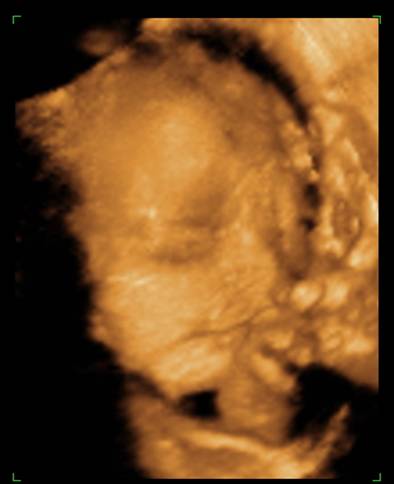

Voltunk 4D-n, rakok fel képeket mindjárt. (apja oda sem nézett, amikor mutatták az arcocskáját, csak nyavajgott, hogy mikor van már vége, érdemes volt elvinni...) De egyre kisebbnek mérik ezt a babát, és kezdek aggódni. Inkább 29 hetes méretei vannak, mint 30... És a súlya még mindig csak 1366, közben itt már mindenkinek minimum másfél kiló fölötti... :cry:

na, még ezeket megmutatom a kis pöttömről:

Kép

Boruska Fel a fejjel! Aludj egy jót! Embered biztos csak nyűgös volt, majd holnap biztos örömmel nézegeti édes kismanótokat a képeken. És miként sok okos már írta, a méretek csak átlagok, s ezek ugye a nagyobbakból és a kisebbekből tevődnek össze. Könnyebb megszülni egy 3 kg-os babát, mint egy 4,5 kg-t :) . És 1 hetes méret eltérés igazán semmitmondó. Valamint a súlybecslés az egyik legbizonytalanabb tényező, szóval ezen tényleg ne aggódj! Az utolsó képen én úgy látom mosolyog Berci. Álmodj ezzel a kis mosollyal!